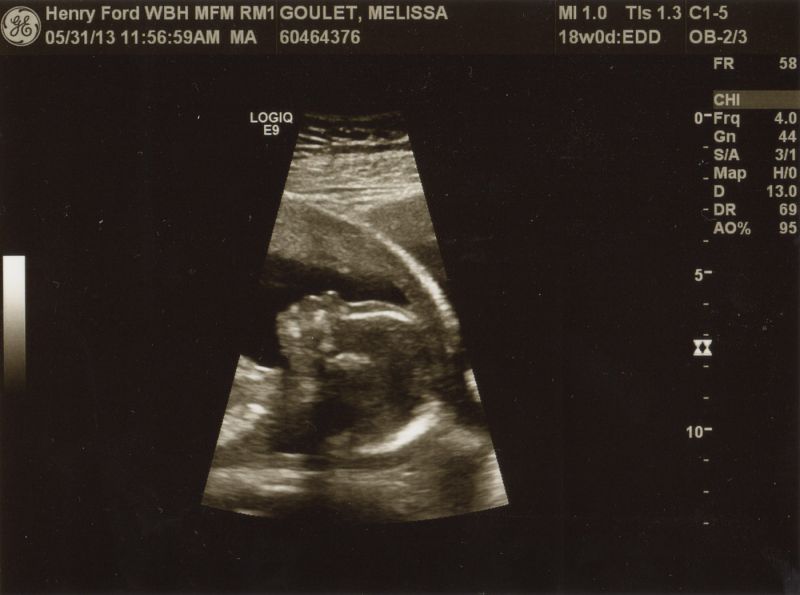

Read ArticleWe have been counting down to week 18 for months! This is the week that our anatomy scan was scheduled for :) As you may have read, we are having a BOY! :) This was the first ultrasound we had the...